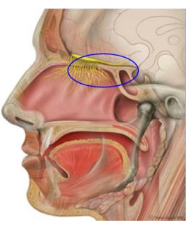

Direct nose-to-brain drug delivery circumvents the blood-brain-barrier and has multiple advantages over ... 扩展阅读